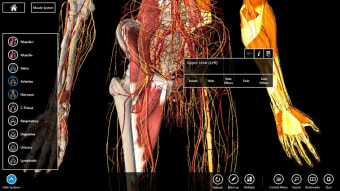

Mudah untuk memeriksa tubuh secara mendetail

Essential Anatomy sangat mudah digunakan. Fungsi pencarian adalah yang paling Anda butuhkan jika Anda sedang belajar meskipun Anda dapat bersenang-senang hanya dengan menjelajahi dan memutar tubuh. Anda dapat melepaskan lapisan otot dan jaringan untuk mengungkapkan apa yang ada di bawahnya, yang memberi Anda gambaran yang lebih baik tentang cara kerja tubuh daripada hanya membacanya di buku.

Selain itu, ada Alat penanda jika Anda hanya ingin menyimpan bagian tertentu yang ingin Anda kembalikan nanti dan Anda dapat mengisolasi tampilan tubuh berdasarkan jenis bagian (misalnya otot, arteri, vena, dll.).